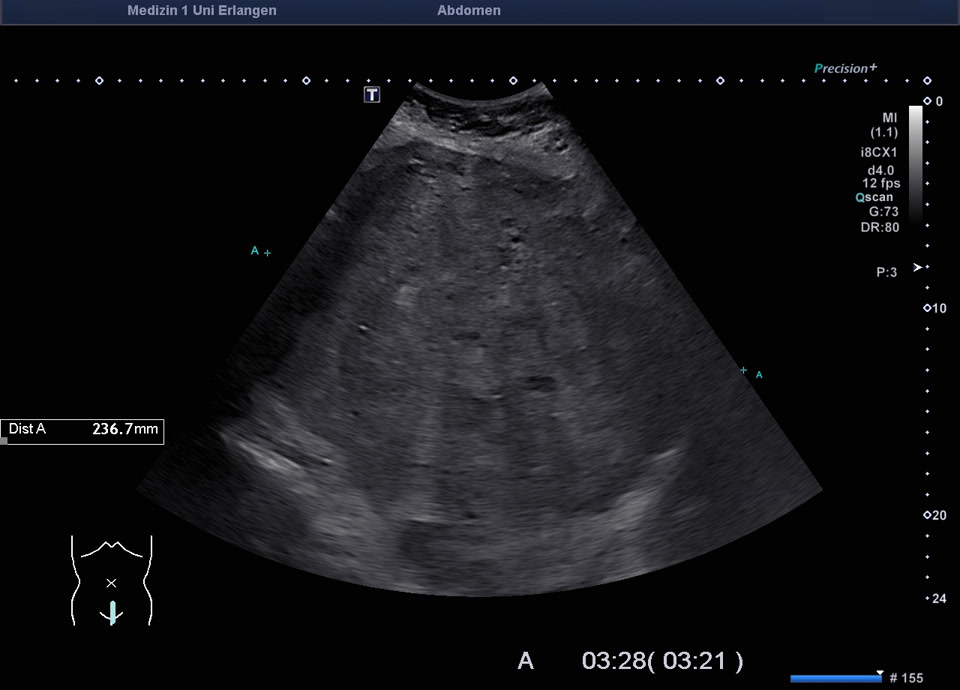

Uterus

• Uterine fibroid